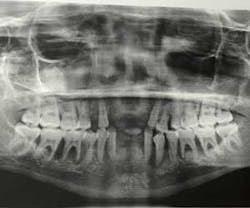

A panoramic radiograph (figure 8) and cone beam CT (CBCT) scan were obtained for evaluation of alveolar bone height and width and all sinus and mental foramen positions.

Due to the aggressive bone loss of the periodontal disease type, a more conservative approach was possible and bone removal was carefully planned if it would become necessary.

Due to the aggressive nature of the disease process, the previously resorbed alveolar bone was very adequate for placement and conversion of the mandibular and maxillary prosthesis.

In the maxilla and mandible, distal implants were placed at proper 30- to 45-degree angles, avoiding sinus perforation and trauma to the mental foramen, respectively.

Anterior implants were placed straight, with the exception of the maxillary left implant placed to avoid a previously developed periodontal defect. All implants were grafted with a combination of mineralized and demineralized human bone allografts, and remaining sockets bone-grafted to enhance alveolar ridge preservation (figure 10). (2)